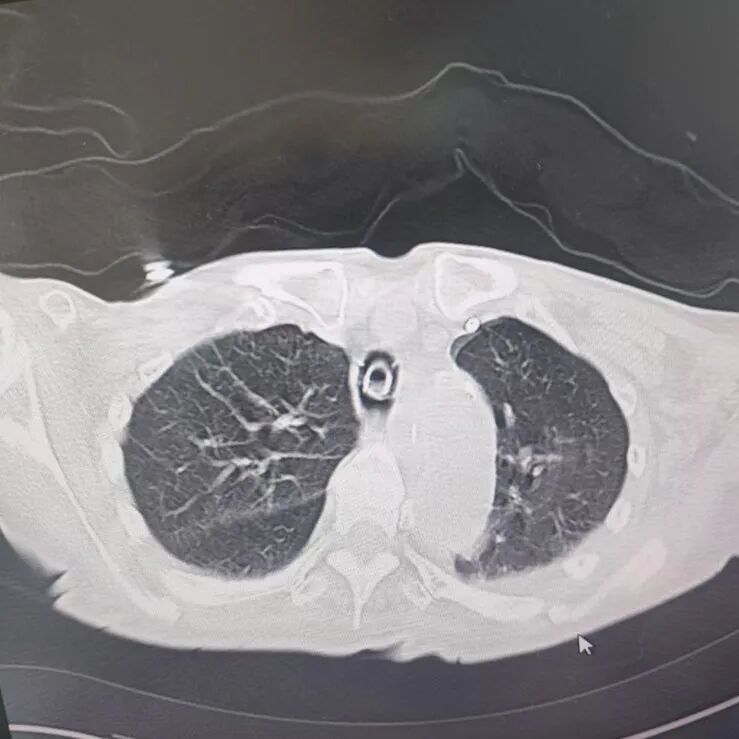

引言 / / Introduction 年近8旬的陈阿姨(化名)因脑梗长期瘫痪在床,康复期间突然高烧不退,体温升至39℃,在抗感染过程中,她并发高渗性脱水,病情急剧恶化,被紧急送入ICU。此时,她已气管切开,依靠呼吸机维持呼吸,并伴有低蛋白血症、低钾高钠血症及房颤等多种危重情况,命悬一线! PART. 01 多重泛耐药菌叠加大量基础病 治疗陷入“死胡同” 呼吸与危重症医学科及ICU通力协作,稳住患者生命体征。治疗过程中,进一步的病原学检查结果令人心惊:陈阿姨的肺部遭遇多种“超级细菌”混合侵袭,包括铜绿假单胞菌、鲍曼不动杆菌、嗜麦芽窄食单胞菌、金黄色葡萄球菌、木糖氧化无色杆菌、粘质沙雷菌等高度耐药菌,堪称耐药菌“大本营”。这些细菌对常用抗生素几乎全部耐药,治疗难度高,死亡率高。 治疗前患者肺部影像 PART. 02 多学科强强联手 量身定制攻坚方案 面对无药可用的困境,呼吸科没有放弃!宋刚主任带领团队联合药学部、检验科、重症医学科成立多学科治疗组,根据患者身体情况实时调整用药,逐一攻破耐药菌。这场与“超级细菌”的拉锯战持续了30多个日夜。 在医护日夜坚守和家属全力配合下,陈阿姨的感染终于被遏制:高烧退了,肺部阴影消散了!就在即将宣告胜利时,又发现她存在泌尿感染问题,随即转入泌尿外科协同治疗。当宋主任回访时,看到陈阿姨精神焕发、体温平稳,所有参与救治的人都感慨万分!这场救治,正是呼吸与危重症医学科攻坚耐药菌硬实力的生动体现! 治疗后患者肺部影像 从“无药可用”到“绝处逢生”,此次成功救治,集中体现了呼吸与危重症医学科以耐药菌精准诊治为核心的学科特色与技术优势。面对一次次的严峻挑战,科室始终秉持“生命至上、知难而进”的信念,以多学科协作为平台,凭借个体化精准用药策略,为患者寻找生机,为更多陷入困境的患者和家庭带去了实实在在的希望。 PART. 03 人民医院 人民名医 宋刚 主任医师 ·葫芦岛市第二人民医院呼吸与危重症医学科主任 ·辽宁省生命科学学会东北呼吸与危重症医学(PCCM)分会辽宁省基层委员会副主任委员 ·辽宁省细胞生物学学会放射粒子治疗专业委员会理事 ·辽宁省抗击新冠肺炎疫情先进个人 ·葫芦岛市劳动鉴定委员会专家库成员 ·葫芦岛市医学会呼吸内科学分会第三届委员会副主任委员 专业特色:擅长呼吸系统疑难及急危重患者的救治,如急慢性支气管炎、支气管哮喘、慢性阻塞性肺疾病、肺炎、肺栓塞、肺癌、间质性肺疾病、睡眠呼吸暂停综合征等,尤其擅长有创无创机械通气、支气管镜下相关检查及治疗(TBNA、气道支架置入术、球囊扩张等)、全肺灌洗术等领先技术,发表国家级期刊多篇。